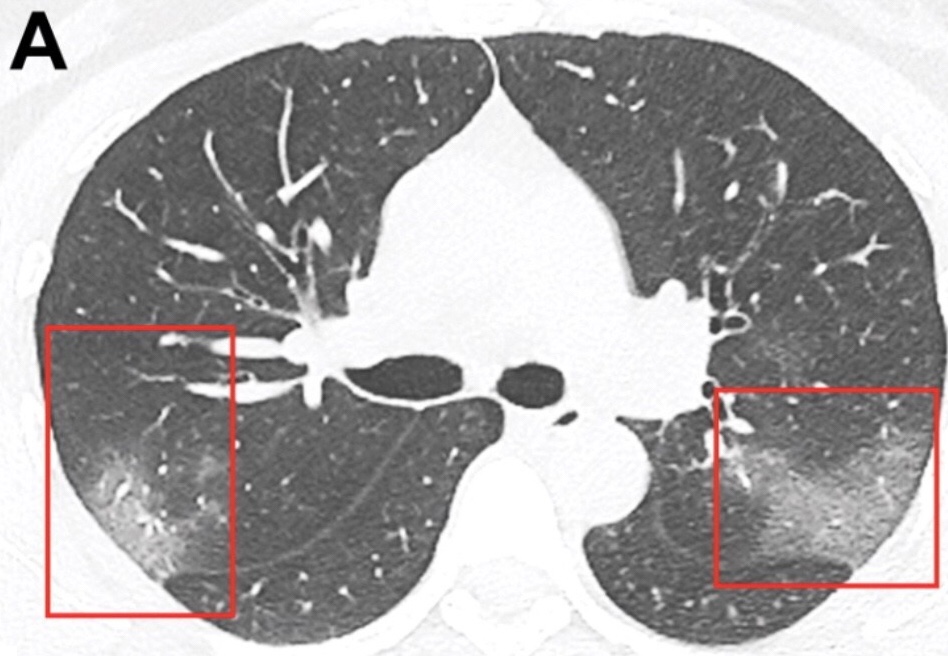

In the first half, I celebrated with patients who had reached this momentous day in their pandemic journey, a day when they get to hit back against Covid, make antibodies prophylactically. In the second, I picked up my stethoscope to listen to the lungs of a 40yo F with Covid-pneumonia.